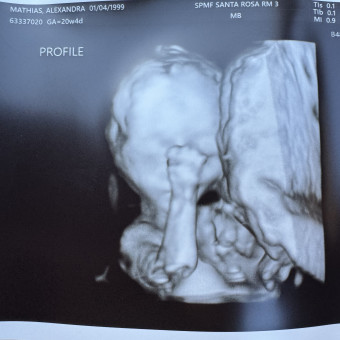

Baby Kaden Mathias

Allie & Dylan Mathias

Santa Rosa, CA